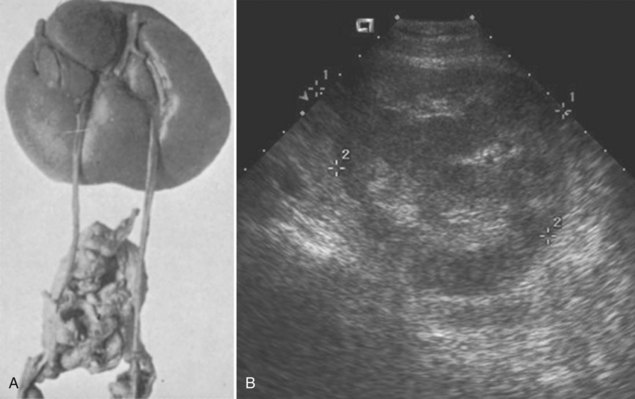

Parenchymal development was thought to be controlled by an unidentified substance that limited the amount of functioning renal tissue. Nature has created, albeit rarely, a condition in which three separate kidneys can form. In this condition, the two main kidneys are usually normal and equal in size, whereas the third is small. The supernumerary kidney is truly an accessory organ with its own collecting system, blood supply, and distinct encapsulated parenchymal mass. It may be either totally separate from the normal kidney on the same side or connected to it by loose areolar tissue (Geisinger, 1937). The ipsilateral ureters may be bifid or completely duplicated. The condition is not analogous to a single kidney with ureteral duplication in which the collecting systems drain portions of one parenchymatous mass surrounded by a single capsule.

The supernumerary kidney is reniform but generally smaller than the main ipsilateral kidney. In about one third of cases, the kidney or its collecting system is abnormal. In almost half of the reported cases, the collecting system is severely dilated with thin parenchyma suggesting obstruction.

The ureteral interrelationships on the side of the supernumerary kidney can be variable (Kretschmer, 1929). Convergence of the ipsilateral ureters distally to form a common stem and a single ureteral orifice occurs in 50% of the cases (Exley and Hotchkiss, 1944; N’Guessan and Stephens, 1983), which suggests “a bud off of a bud” situation. Two completely independent ureters, each with its own entrance into the bladder, are seen in the other 50% of cases. The Weigert-Meyer principle (see Chapter 111) usually is followed, but in 10%, the caudal kidney has a ureter that does not follow the rule and enters the trigone below the ipsilateral ureter (Tada et al, 1981) (Fig. 117–7). Rarely, the supernumerary kidney has a completely ectopic ureter opening into the vagina or introitus (Rubin, 1948; Carlson, 1950). Individual case reports have described calyceal communications between the supernumerary and the dominant kidney, or fusion of the dominant kidney’s ureter with the pelvis of the supernumerary kidney (Kretschmer, 1929) to create a single distal ureter that then enters the bladder (Fig. 117–8). The vascular supply to the supernumerary kidney is anomalous and depends on its position in relation to the major ipsilateral kidney. Most investigators believe that the blood supply to the individual parenchymal masses should be separate to consider this a true supernumerary kidney (Kaneoya et al, 1989).